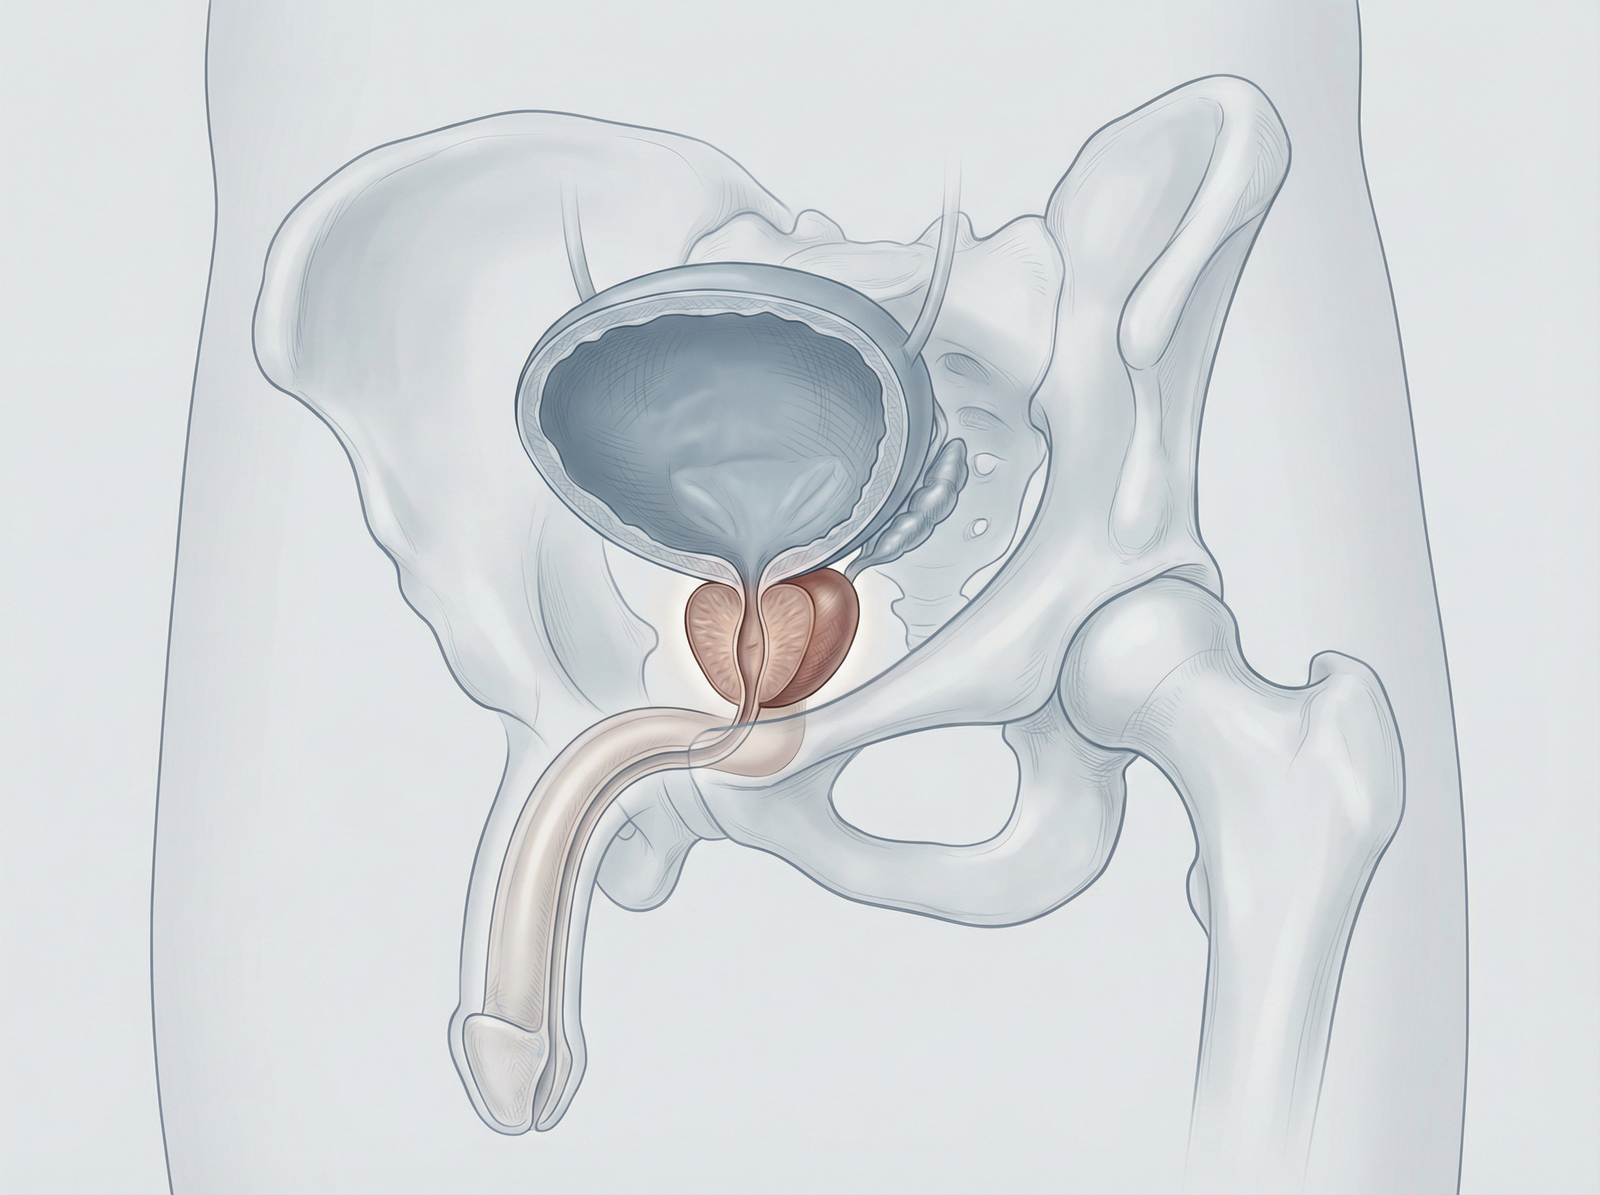

Enucleazione laser a fibra di tulio della prostata (ThuFLEP). Tecnica avanzata e mininvasiva per il trattamento dell’ipertrofia prostatica benigna, che consente la rimozione precisa del tessuto in eccesso con minimo sanguinamento. Recupero più rapido, maggiore sicurezza e miglioramento significativo dei sintomi urinari, per una migliore qualità della vita.

Hai problemi ad urinare a causa dell’ingrossamento della prostata? Presso la clinica Fabjan in Slovenia eseguiamo l’enucleazione laser della prostata con il laser a fibra di Thulium – ThuFLEP.